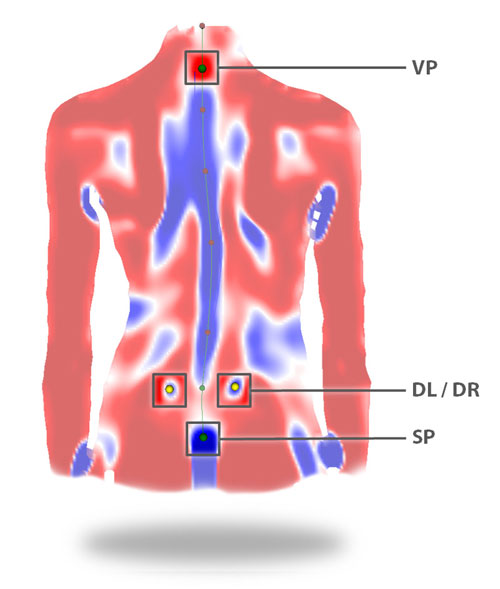

- С помощью DIERS formetric 4D осуществляется быстрая и точная диагностика заболеваний позвоночника и нарушения осанки. Устройство функционирует по принципу видеорастростереографии. На спину пациента проецируются линии, составляющие сетку. Полученная картина дает возможность сформировать модель спины и позвоночника без использования проникающего излучения. Именно поэтому диагностика и лечение позвоночника с применением прибора DIERS formetric 4D совершенно безопасны для организма человека.

- система автоматически определяет анатомические маркеры, гарантируя надежность полученных результатов;

- Осаночные болевые синдромы (крестцово-подвздошного сочленения, грудного отдела, поясничного отдела)

- 3D-Реконструкция поверхности спины и позвоночника без рентгеновского облучения

- Уменьшение влияния естественных колебаний тела на результат исследования для самых точных результатов обследования